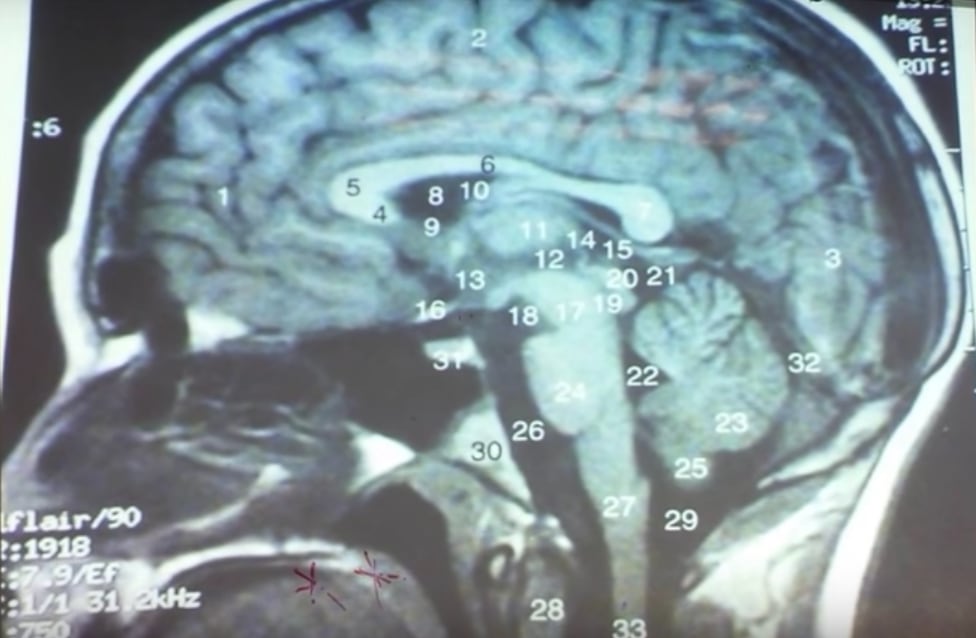

¿Dónde está el lóbulo parietal?

El lóbulo parietal está ubicado detrás del lóbulo frontal, pero los separa un surco central. Está por encima del occipital y del temporal y por detrás del frontal. Como muchas otras secciones del cerebro este lóbulo trabaja en conjunto con otras partes.

Este lóbulo se divide en cinco partes distintas que son:

- Giro postcentral o área 3 de Brodmann: En este sector se localiza el área somatosensorial primaria, encargada de recibir y procesar la información sensorial o de los sentidos.

- Corteza parietal posterior: Esta sección sirve para procesar todos los estímulos que vemos y para coordinar los movimientos.

- Lóbulo parietal superior: Esta parte ayuda en la orientación espacial y la motricidad fina.

- Lóbulo parietal inferior: Se encarga de relacionar las expresiones faciales con las emociones, así como ejecutar las operaciones matemáticas, el lenguaje y la expresión corporal.

- Área sensorial primaria: aquí se procesa toda la información relativa a la piel como el calor, el frío o el dolor.